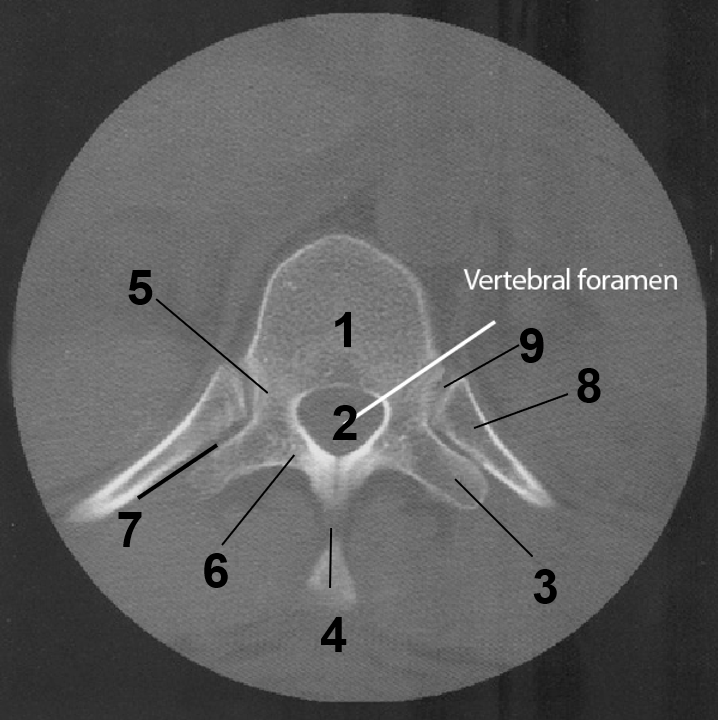

1

Dens

2

Lateral Masses

3

Atlas

4

Atlanto-occipital joint

5

Body of the axis

6

C2-C3 Intervertebral disc

7

C3